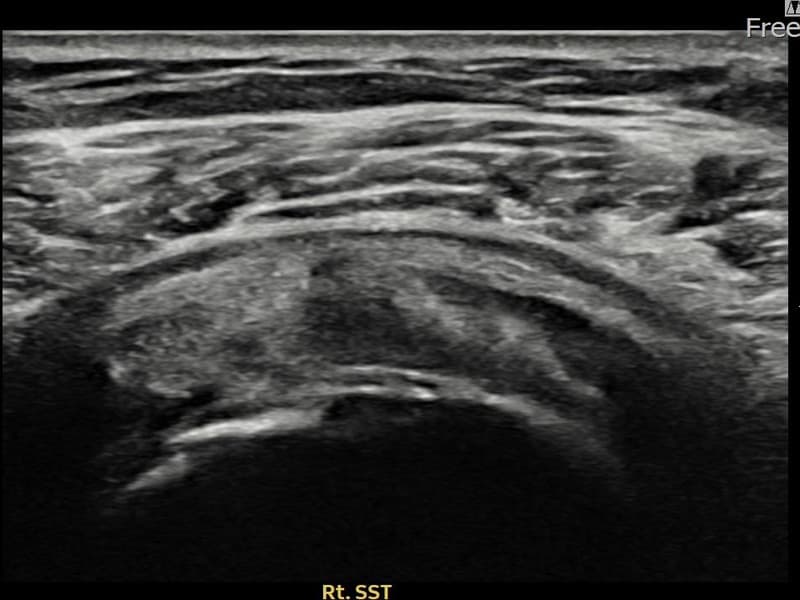

术后

术前超声确认右侧 冈上肌腱 关节面侧部分撕裂,右侧冈上肌腱回声不连续伴肌腱缺损(7mm × 3mm (肌腱厚度约30%缺损))。术后超声显示撕裂部位充满再生组织,肌腱连续性恢复,回声模式正常化。